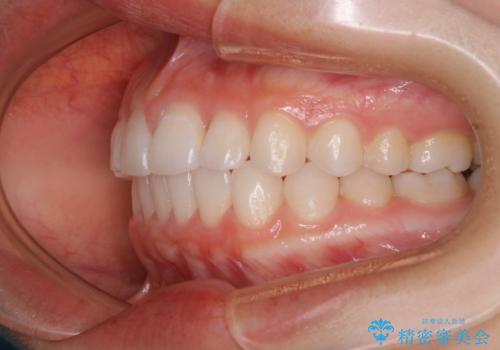

前歯のがたつきをインビザラインで治療

- 上下前歯のがたつきが気になるとの事で来院された患者様です。がたつきの程度が軽度であったため、インビザラインライトにて治療をおこないました。

がたつきの程度が軽度であったことと、インビザラインを正しく装着して頂けたことで短期間で治療終了することが出来ました。